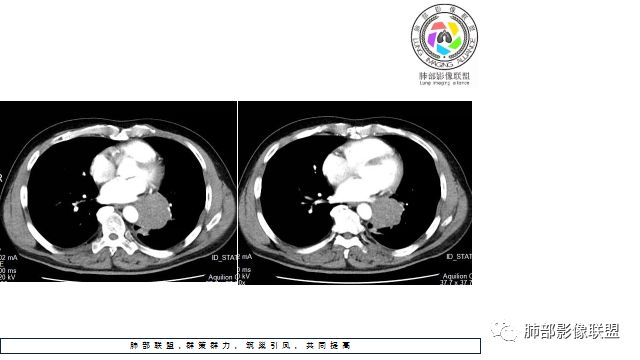

1.左下肺门区巨大肿块,支气管显示不清,轻度阻塞性炎症,没有明显肺不张,提示管腔受压狭窄可能性大于堵塞,这较少见于鳞癌。

2.病灶边缘光滑,未见明显分叶、毛刺,未见明显强化,这符合腺癌影像学特点,却符合神经内分泌癌表现。

3.病灶内密度均匀,轻到中度均匀强化,大病灶未见明显液化坏死区及空洞,不符合鳞癌而符合小细胞肺癌特点。

4.病灶内有肺动脉走形,血管局部受压,未见破坏,病灶乏血供,呈血管包埋或血管造影征;侵袭性力强及破坏力弱、血管漂浮都符合SCLC,所以鳞癌的可能性也不大。

5.左肺门块影或淋巴结肿大,竭力挤兑肺门血管结构,呈冰冻肺门;有时候SCLC可以单独呈现冰冻肺门,而没有没有冰冻纵隔。